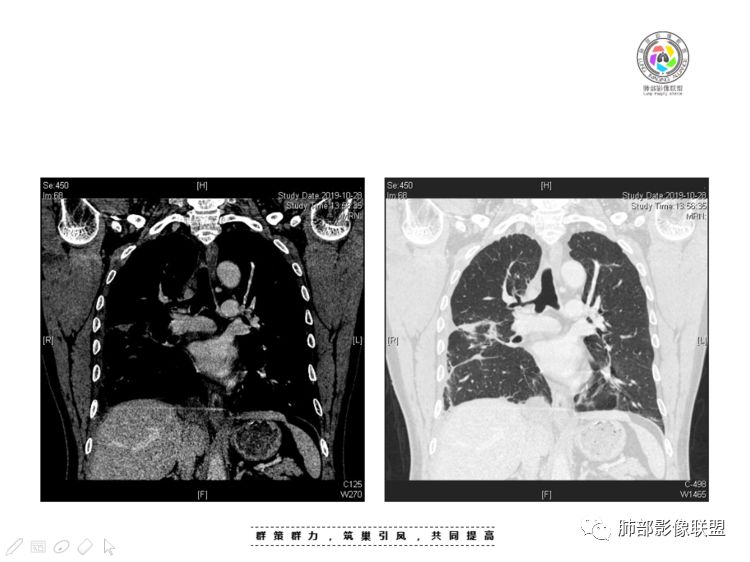

本例纵隔与肺内两处病变,回顾总结分析:

1、右肺内病灶,病灶呈结节样,边缘欠规则,局部膨隆,叶间裂胸膜牵拉凹陷,再看相应支气管腔堵塞截断,临床资料胸水中查到癌细胞,均提示病灶倾向恶性,腺癌的病理意见与之相吻合。

黄勇老师总结,腺癌如果与胸膜、叶间裂紧贴或伴胸膜凹陷,胸膜、叶间裂多发结节,应当高度怀疑腺癌转移。

2、前纵隔内病灶囊实性混杂密度病灶,囊性病灶主要位于右侧,张力较高,有分隔影,囊壁右侧缘光整,病灶左侧实性部分边界不清明显强化,病灶肺瘤交界面大部分边界清楚,部分模糊。

前纵隔肿块伴囊变坏死常见以有胸腺瘤、胸腺癌、淋巴瘤和生殖细胞肿瘤。

胸腺瘤/胸腺癌:病灶内那么大的囊,常规考虑B型以上胸腺瘤,囊内有分隔影,病灶周围脂肪间隙模糊,常规考虑侵袭性胸腺瘤或胸腺癌,若侵袭性胸腺瘤,常侵犯胸膜、心包,很少累及肺。胸腺癌易侵犯胸膜、肺并纵隔淋巴结及远处转移。但肺内腺癌形态更符合原发灶。胸膜及叶间裂转移则即可来自肺,也可来自胸腺癌。

尽管前纵隔病灶缺乏相关病理资料,但是小编还是认为肺内与纵隔病灶以二元论解释。只是肺内恶性病灶引发的胸膜改变可能会影响我们对纵隔病灶的判断。